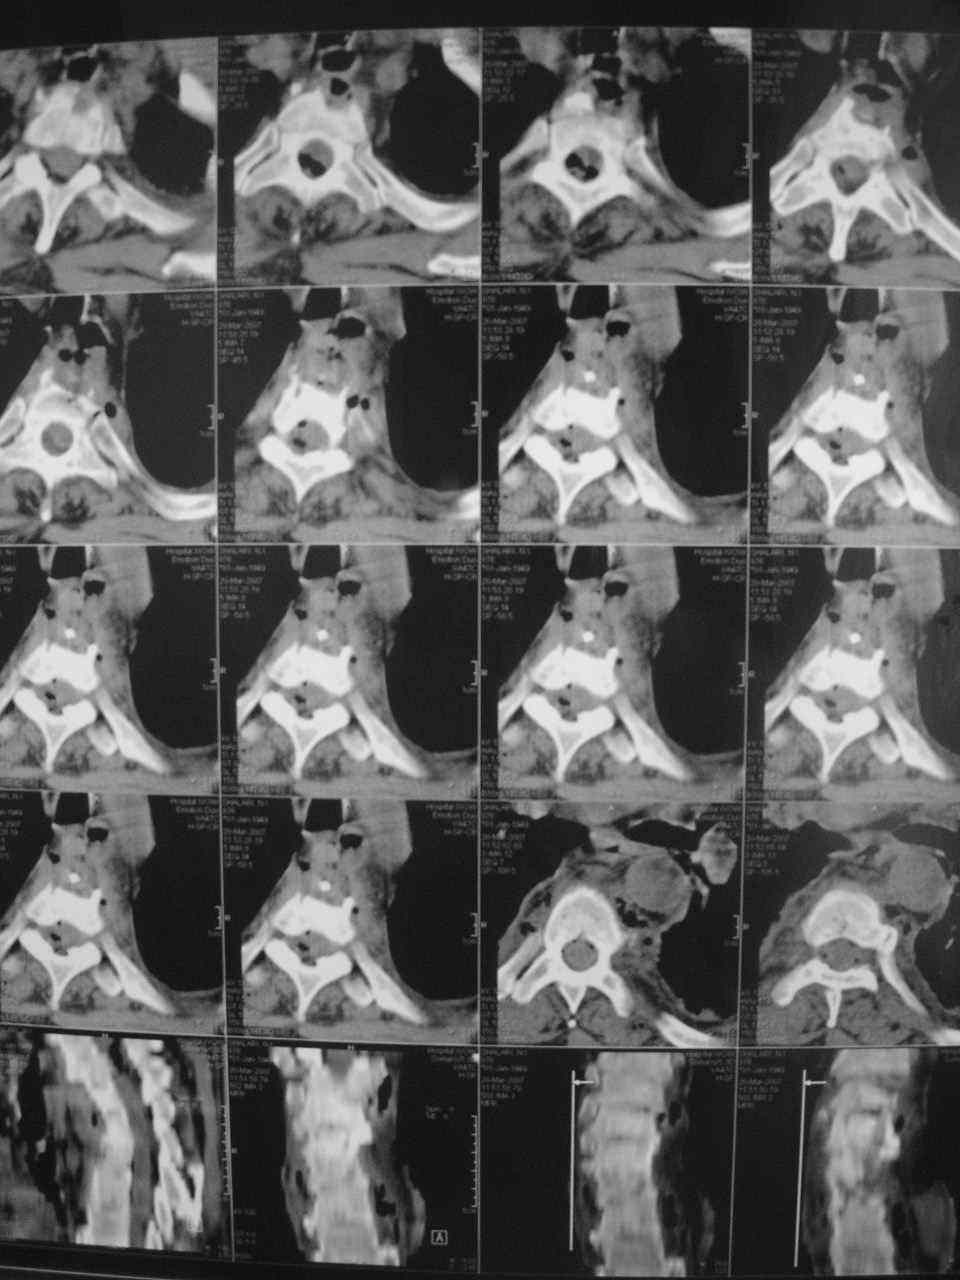

Назначенное рутинное лечение остеохондроза с включением НПВС было без эффекта. На фоне нарастающего болевого синдрома, 15. 03.07 г наступила нижняя параплегия, нарушение функции тазовых органов по типу острой задержки мочи. Больной переведен в ОРиТ, где были выполнены дополнительные методы обследования:

1. Rо-графия грудного и поясничного отделов позвоночника - деструкция с клиновидной деформацией Th5-6. Закл.: застарелый компрессионный перелом? Мт?

Осмотрен урологом, онкологом. Достоверных данных за наличие Мт. не установлено. В связи с неясностью диагноза, был направлен на КТ в Тираспольскую РКБ.

21 марта больной скончался. На вскрытии - внутренние органы без признаков какой-либо патологии. При разведении волокон передней продольной связки в проекции Th4-6 была вскрыта гнойная полость с наличием деструкции тел указанных позвонков, с прорывом гнойника в позвоночный канал. Дуги и отростки позвонков - без признаков поражения. Гной сливкообразной консистенции, зеленоватого цвета. Гнойных затеков в мягких тканях также не обнаружено. Таким образом, выставлен п\а диагноз: гнойный остеомиелит тел Th4-6 c прорывом в позвоночный канал.